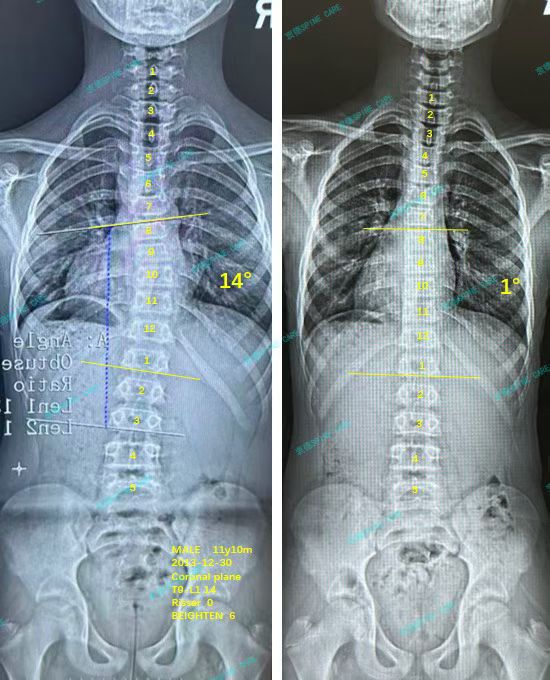

案例主人:Leo 发现侧弯年龄:11岁 侧弯情况:Cobb角度14度

衷德脊柱的康复师都很亲和,每次训练老师会耐心教我,杨博士也会看我的体态,在训练了3个月之后,拍片显示我的胸弯角度从14度降低到了1度,体态也明显改善了,我非常开心~

The rehabilitation therapists at Zhongde Spine are all very kind. Every time during training, the teachers would teach me patiently, and Dr. Yang would also check my posture. After three months of training, the X-ray showed that my thoracic curvature angle had decreased from 14 degrees to 1 degree, and my posture had improved significantly. I'm very happy~